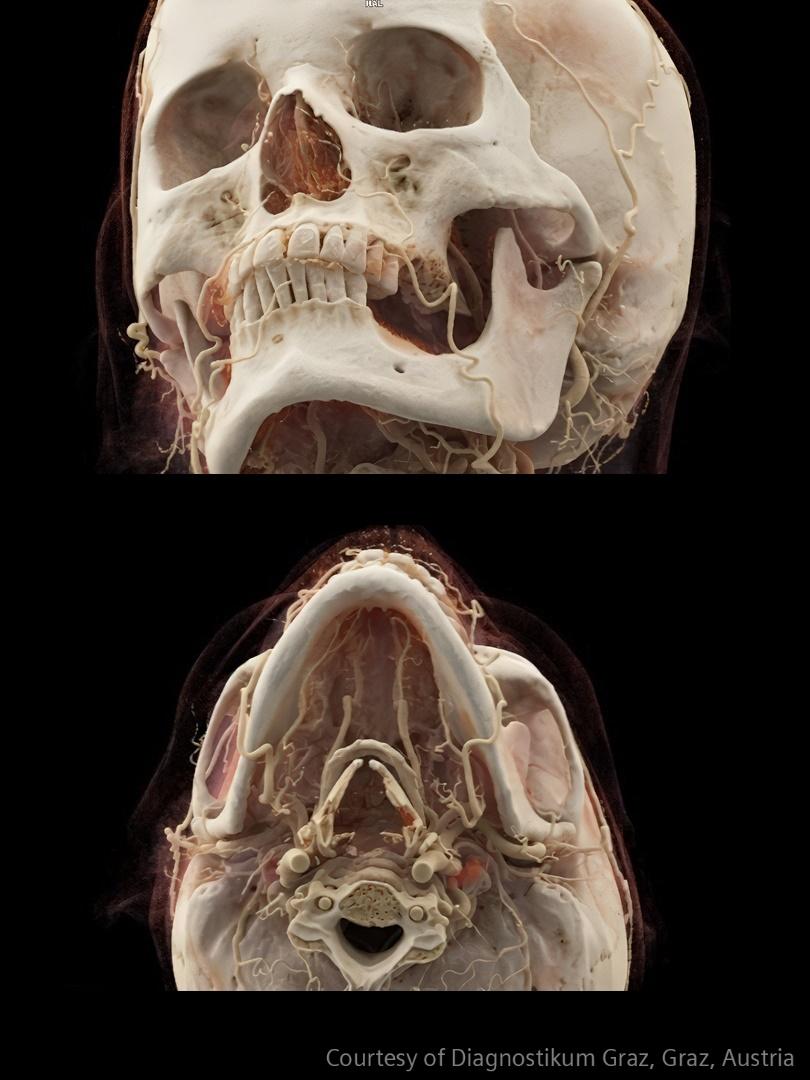

Im Bereich der Schlaganfallversorgung zählt jede Sekunde . Schnelle und präzise Bildgebung ist entscheidend, um das Ausmaß der Hirnschädigung zu beurteilen und die sofortige Behandlung einzusteuern. Angiographie, MRT, CT, Labordiagnostik und Ultraschall sind unverzichtbare Werkzeuge, um Schlaganfalltyp, -bereich und -schwere zu bestimmen. Durch technologische Fortschritte in der Bildgebung sind heute noch schnellere Aufnahmen, eine bessere Auflösung und eine optimierte Darstellung von Gehirnstrukturen und Blutgefäßen möglich. Innovationen wie Perfusionsbildgebung, Echtzeit-Gefäßkartierung und KI-gestützte Diagnostik revolutionieren die Abläufe bei Schlaganfällen und ermöglichen präzise zeitnahe Interventionen.